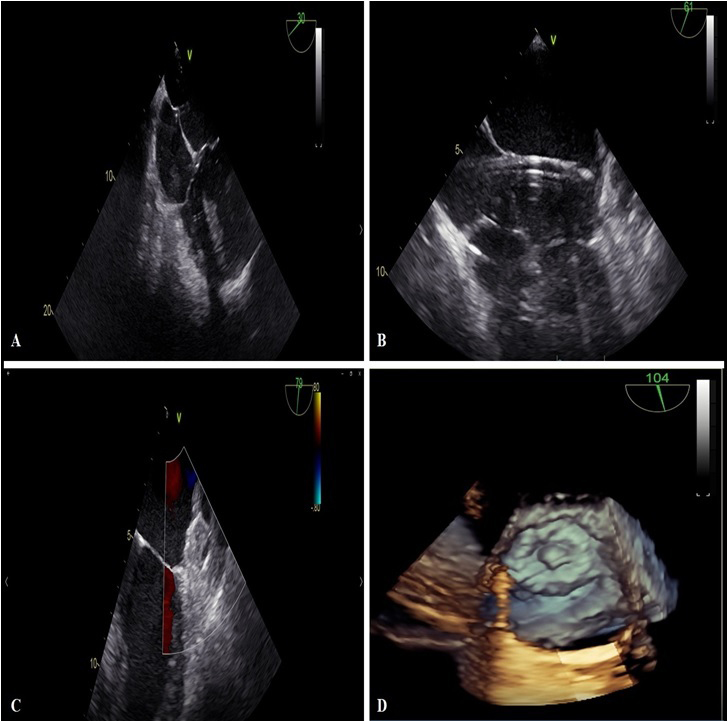

During percutaneous LAAO and TEE monitoring it is necessary that an expert operator accurately identifies the projections useful for a generic re-evaluation at the beginning of the procedure, for the transseptal puncture, for the correct sizing and for the correct positioning of the device (Fig. 1).

Fig. 1.TEE monitoring during percutaneous LAAO with Watchman Flex device. (A) Highlights the transseptal puncture maneuver. (B) Describe device positioning with double curve sheath. (C,D) Highlights in 2 D and 3 D TEE modality the complete occlusion of LAA.